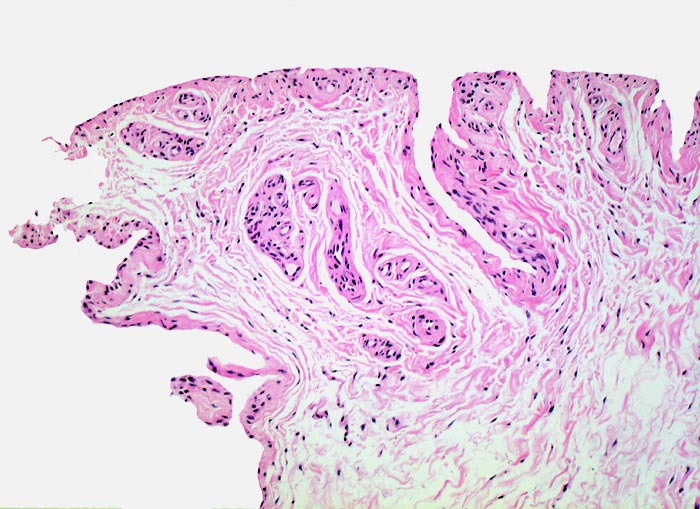

In Abhängigkeit von der Entzündungsdauer werden unterschiedliche morphologische Befunde beschrieben. Die initiale proliferative Phase ist charakterisiert durch eine Hyperplasie der Synovialis, Fibrinexsudate und Gelenkergüsse. In der destruktiven Phase kommt es zur Zerstörung von Gelenkknorpel und gelenknahem Knochen durch Ausbildung eines intraartikulären Pannusgewebes (> 194). Die ausgebrannte Phase ist gekennzeichnet durch eine synoviale Fibrose mit zunehmender Ankylose (= Gelenkversteifung).

Typische histologische Veränderungen sind eine synoviale Zottenhyperplasie, Verbreiterung der Deckzellschicht unter Einschluss mehrkerniger Riesenzellen, Fibrinexsudate und synoviale Ulzerationen, Infiltrate von Lymphozyten teils in Form von Lymphfollikeln, Plasmazellen, neutrophilen Granulozyten, Makrophagen und Siderophagen, sowie Einschlüsse von Knorpel- und Knochenfragmenten (Detritussynovialitis). Die histologischen Befunde der Synovialis korrelieren oft nicht mit den klinischen Angaben. Trotz fortgeschrittener Gelenkdestruktion mit ausgeprägter klinischer Symptomatik können Synovialektomiepräparate nur sehr geringe pathologische Veränderungen zeigen. Oft ist auch nicht mehr zu eruieren, welche Läsionen Folge der Grundkrankheit und welche Folge diverser intraartikulärer Therapien oder begleitender Superinfektionen sind.

Morphologische Merkmale:

• Synovialis mit verplumpten Zotten.

• Stark proliferierte mehrreihige synoviale Deckzellschicht.

• Herdförmig Fibrinauflagerungen durchsetzt von neutrophilen Granulozyten.

• Hyperzelluläres Stroma mit lymphoplasmazellulärem Entzündungsinfiltrat mit Ausbildung von Lymphfollikeln.